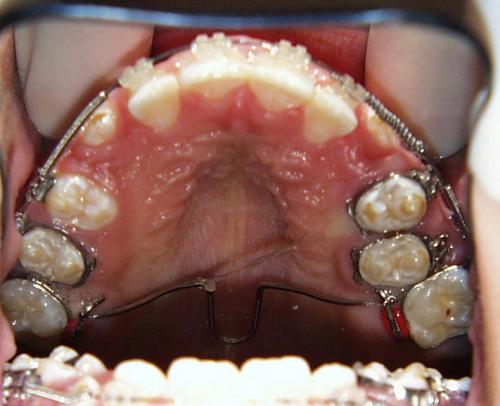

Während der Behandlung

Zunächst wurde der obere Zahnbogen geweitet und mit dem Ausrichten der Schneidezähne begonnen.

Die Zahnbogenmitte wurde eingestellt, die oberen Eckzähne eingeordnet und nach Einbeziehung des unteren Zahnbogens der offene Biß beseitigt.